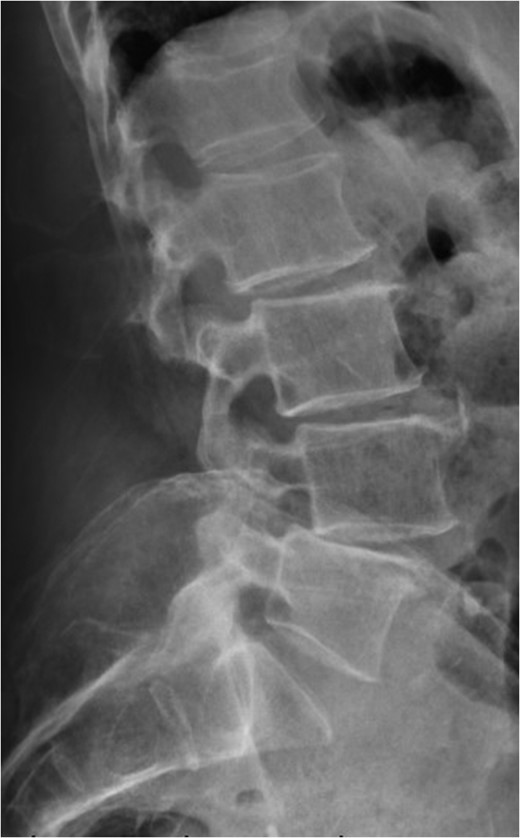

Standing neutral lateral lumbar radiograph obtained the day following the patient's L4–S1 revision decompression and posterior instrumented fusion with TLIF performed at each of these revised levels. A moderate correction of the prior L4-5 anterolisthesis was achieved and the patent's spine and construct appear stable.